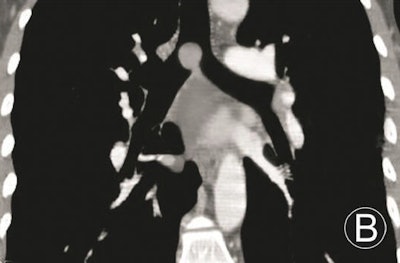

- Intraluminal and extraluminal tumors: These manifest as infiltrated growth along thickened walls, with invasion extraluminally, and masses both intraluminally and extraluminally.

Tumors with dominant intraluminal growth have significant luminal stenoses, the group noted. Tumors with evident extraluminal growth may resemble mediastinum tumors. Tumors with apparent intraluminal and extraluminal growth have large masses and are often obstructive.

The results demonstrated that MPR could not only display the locations, morphologies, internal features, and extramural invasions of primary trachea and main bronchus tumors, along with morphologies and extents of luminal stenoses, it could also measure their longitudinal involvement and distances between main bronchus tumors and trachea carinae. However, due to the 2D images, MPR could not provide a 3D effect, according to the researchers.

Volume-rendered images can handily demonstrate locations, morphologies of primary trachea and main bronchus tumors, and morphologies and extents of luminal stenoses, and it can measure the longitudinal involvements and distances between main bronchus tumors and trachea carinae. However, volume rendering can't display the internal features of tumors and extramural invasions, they noted.